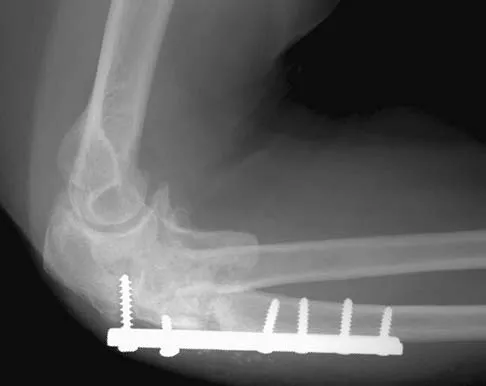

A 54-year-old woman sustained an elbow injury 3 months ago that was treated with open reduction and internal fixation. She now reports pain and limited elbow motion. Radiographs are shown in Figures 10a and 10b. Treatment should now consist of

Explanation